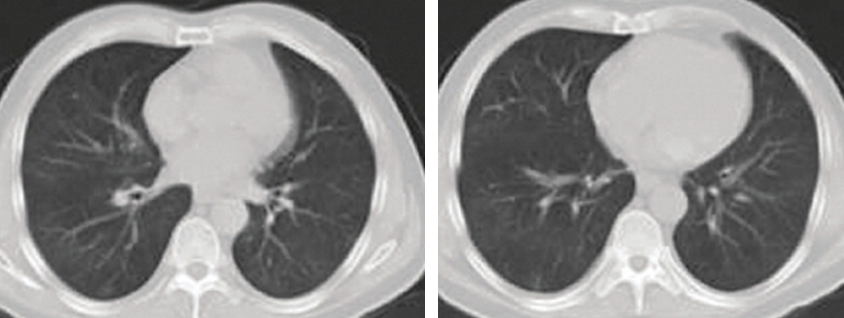

Case 2: Male, 60 years old, resident of Wuhan, presented to the district hospital with fever and rigors, dry cough, aching muscles, breathlessness, fatigue, bloating, and anorexia since 17 January 2020. His CT scan showed an infective appearance in both lungs, and a diagnosis of viral pneumonia was suspected. He received unknown outpatient treatment.

• The patient was discharged with complete clinical and laboratory resolution and almost complete radiological resolution on 10 February 10, 2020.